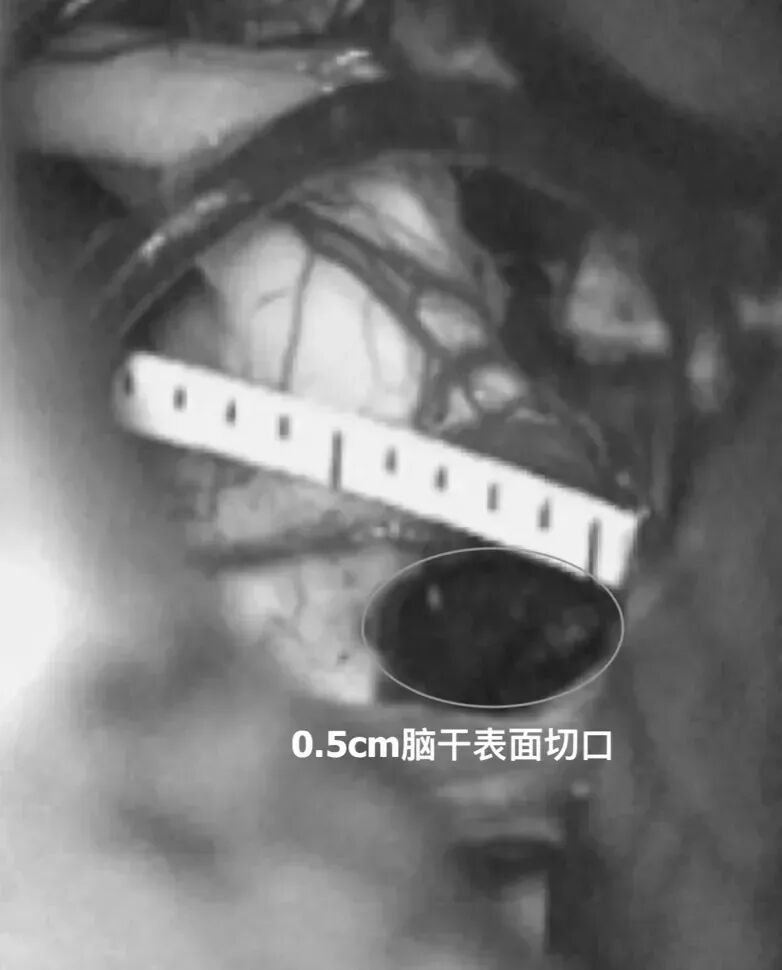

手术由巴教授主刀,采取乙状窦后入路开颅方式,在显微镜下成功全切肿瘤,术中全程实施电生理监测。手术过程顺利,经直尺测量脑干病变切除切口仅3cm,脑干表面切口仅0.5cm,证明巴教授在极小操作空间内实现肿瘤全切的高超技术。